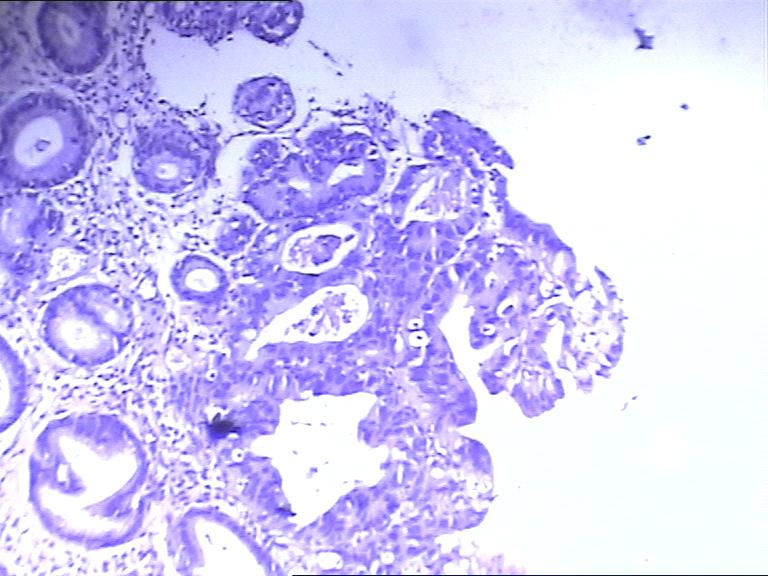

男 63岁 胃镜提示残胃炎

胃镜活检图1

胃镜活检图2

高级别瘤变

高级别上皮内瘤变。他原先是因为什么病做的手术?

低级别病变

bugougaojibie不够高级别,是不是一种炎症反应

2010年2月以低分化腺癌行近段胃癌根治术,术后给予奥沙利铂、5-氟尿嘧啶化、cf等化疗4次。

高级别上皮内瘤变

高级别上皮内瘤变,不知胃镜下病变范围

结构的紊乱考虑手术所致,细胞的异性可能为炎性所致,